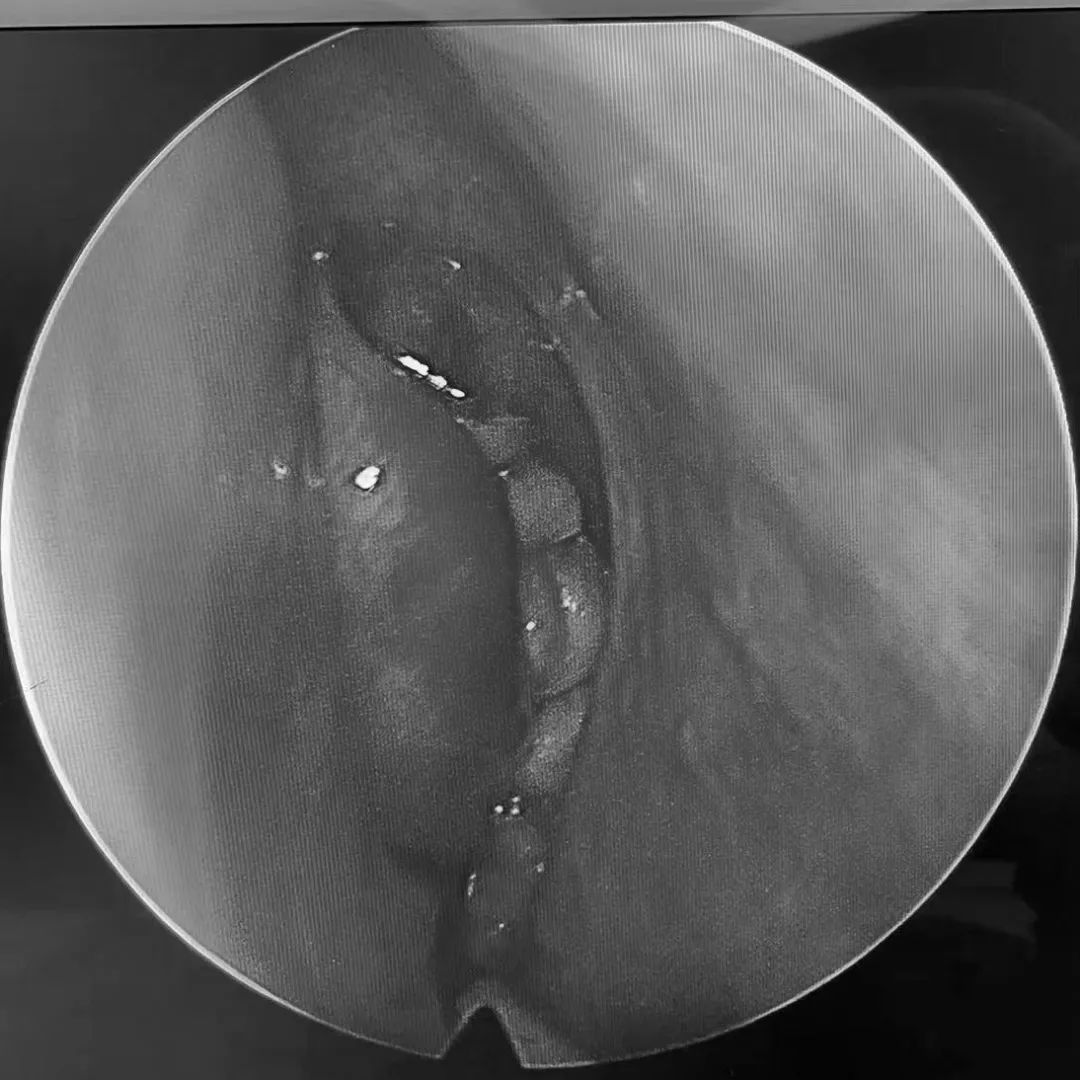

术中影像1

3月21日,耳鼻咽喉主任带领团队为其进行手术。术中,发现余女士的 鼻腔内的炎症已蔓延至上颌骨及眼眶内侧壁。 熊主任见状,立即清除蔓延部位的病变组织。